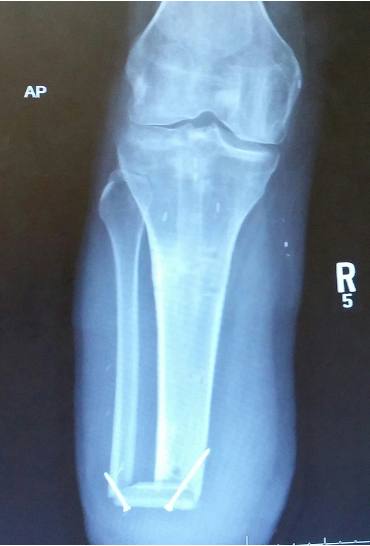

the Ertl procedure is a modification of the ___________ procedure

Ertl

the _____________ procedure installs a bone as a “bridge” between the fibula and tibia to allow for distal end WB